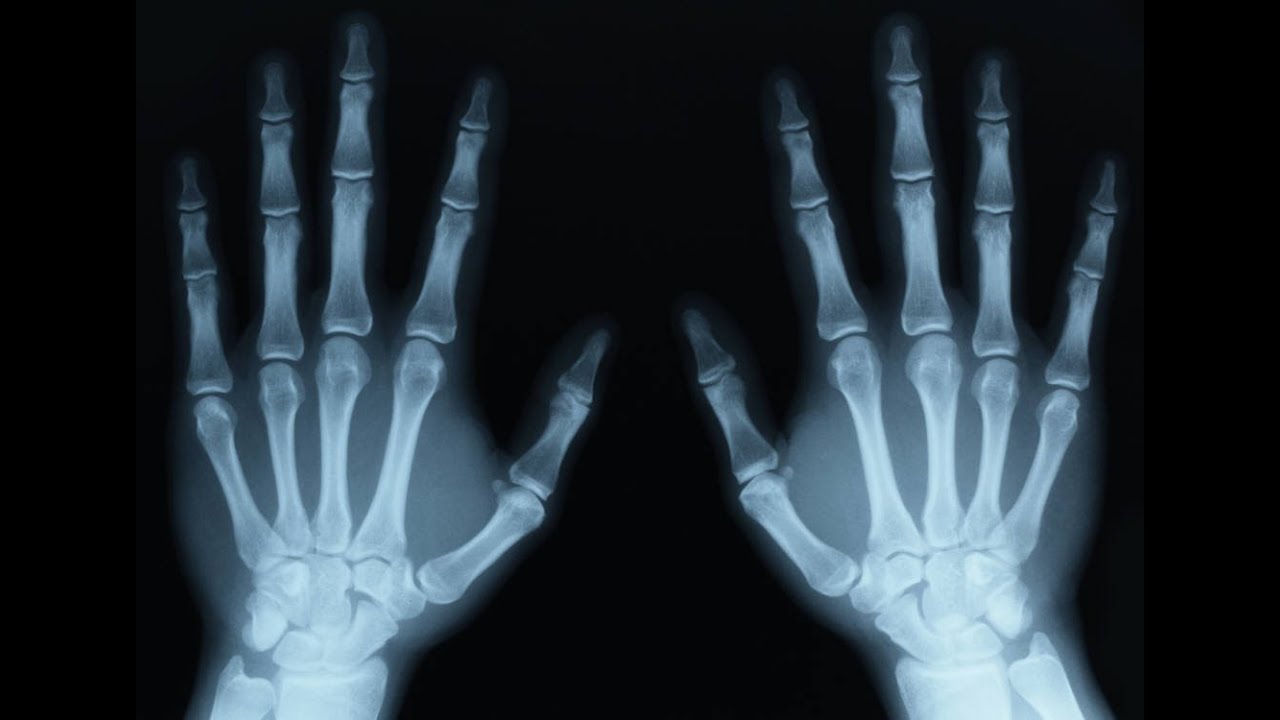

أشعة X، أو الأشعة السينية، هي نوع من الإشعاع الكهرومغناطيسي ذو طاقة عالية وطول موجي قصير جدًا. هذه الأشعة قادرة على اختراق العديد من المواد، بما في ذلك جسم الإنسان، […]